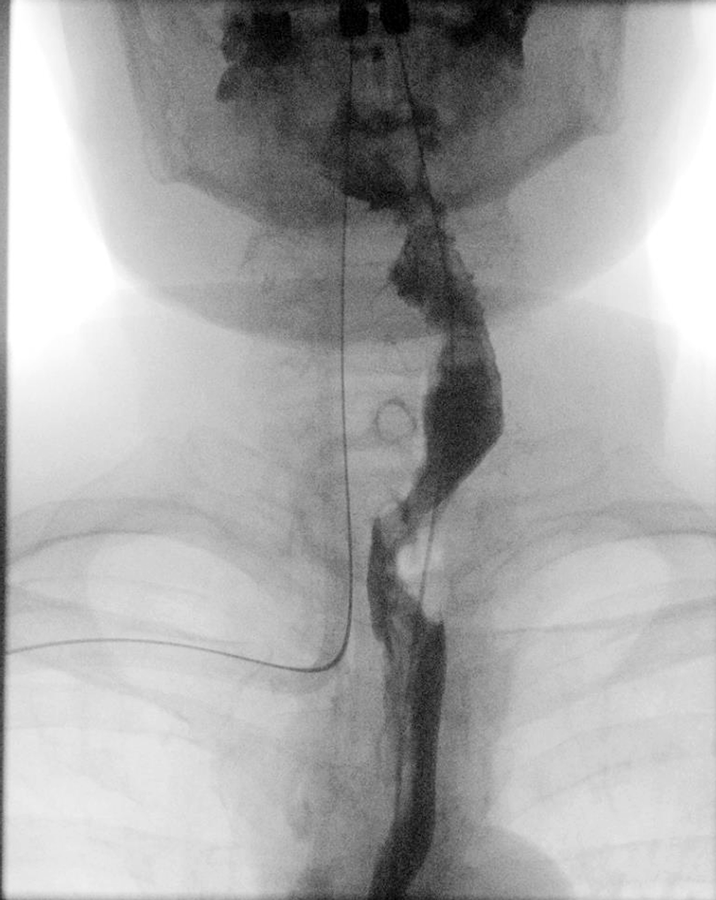

Nach zweiwöchiger oraler Nahrungskarenz zeigte sich im Röntgen-Breischluck eine kontinuierliche Passage, sodass der orale Kost­aufbau begonnen werden konnte.

3. 14 Tage nach dem Eingriff stellte sich der obere Verdauungstrakt im Röntgen-Breischluck regelrecht dar. 3. 14 Tage nach dem Eingriff stellte sich der obere Verdauungstrakt im Röntgen-Breischluck regelrecht dar.